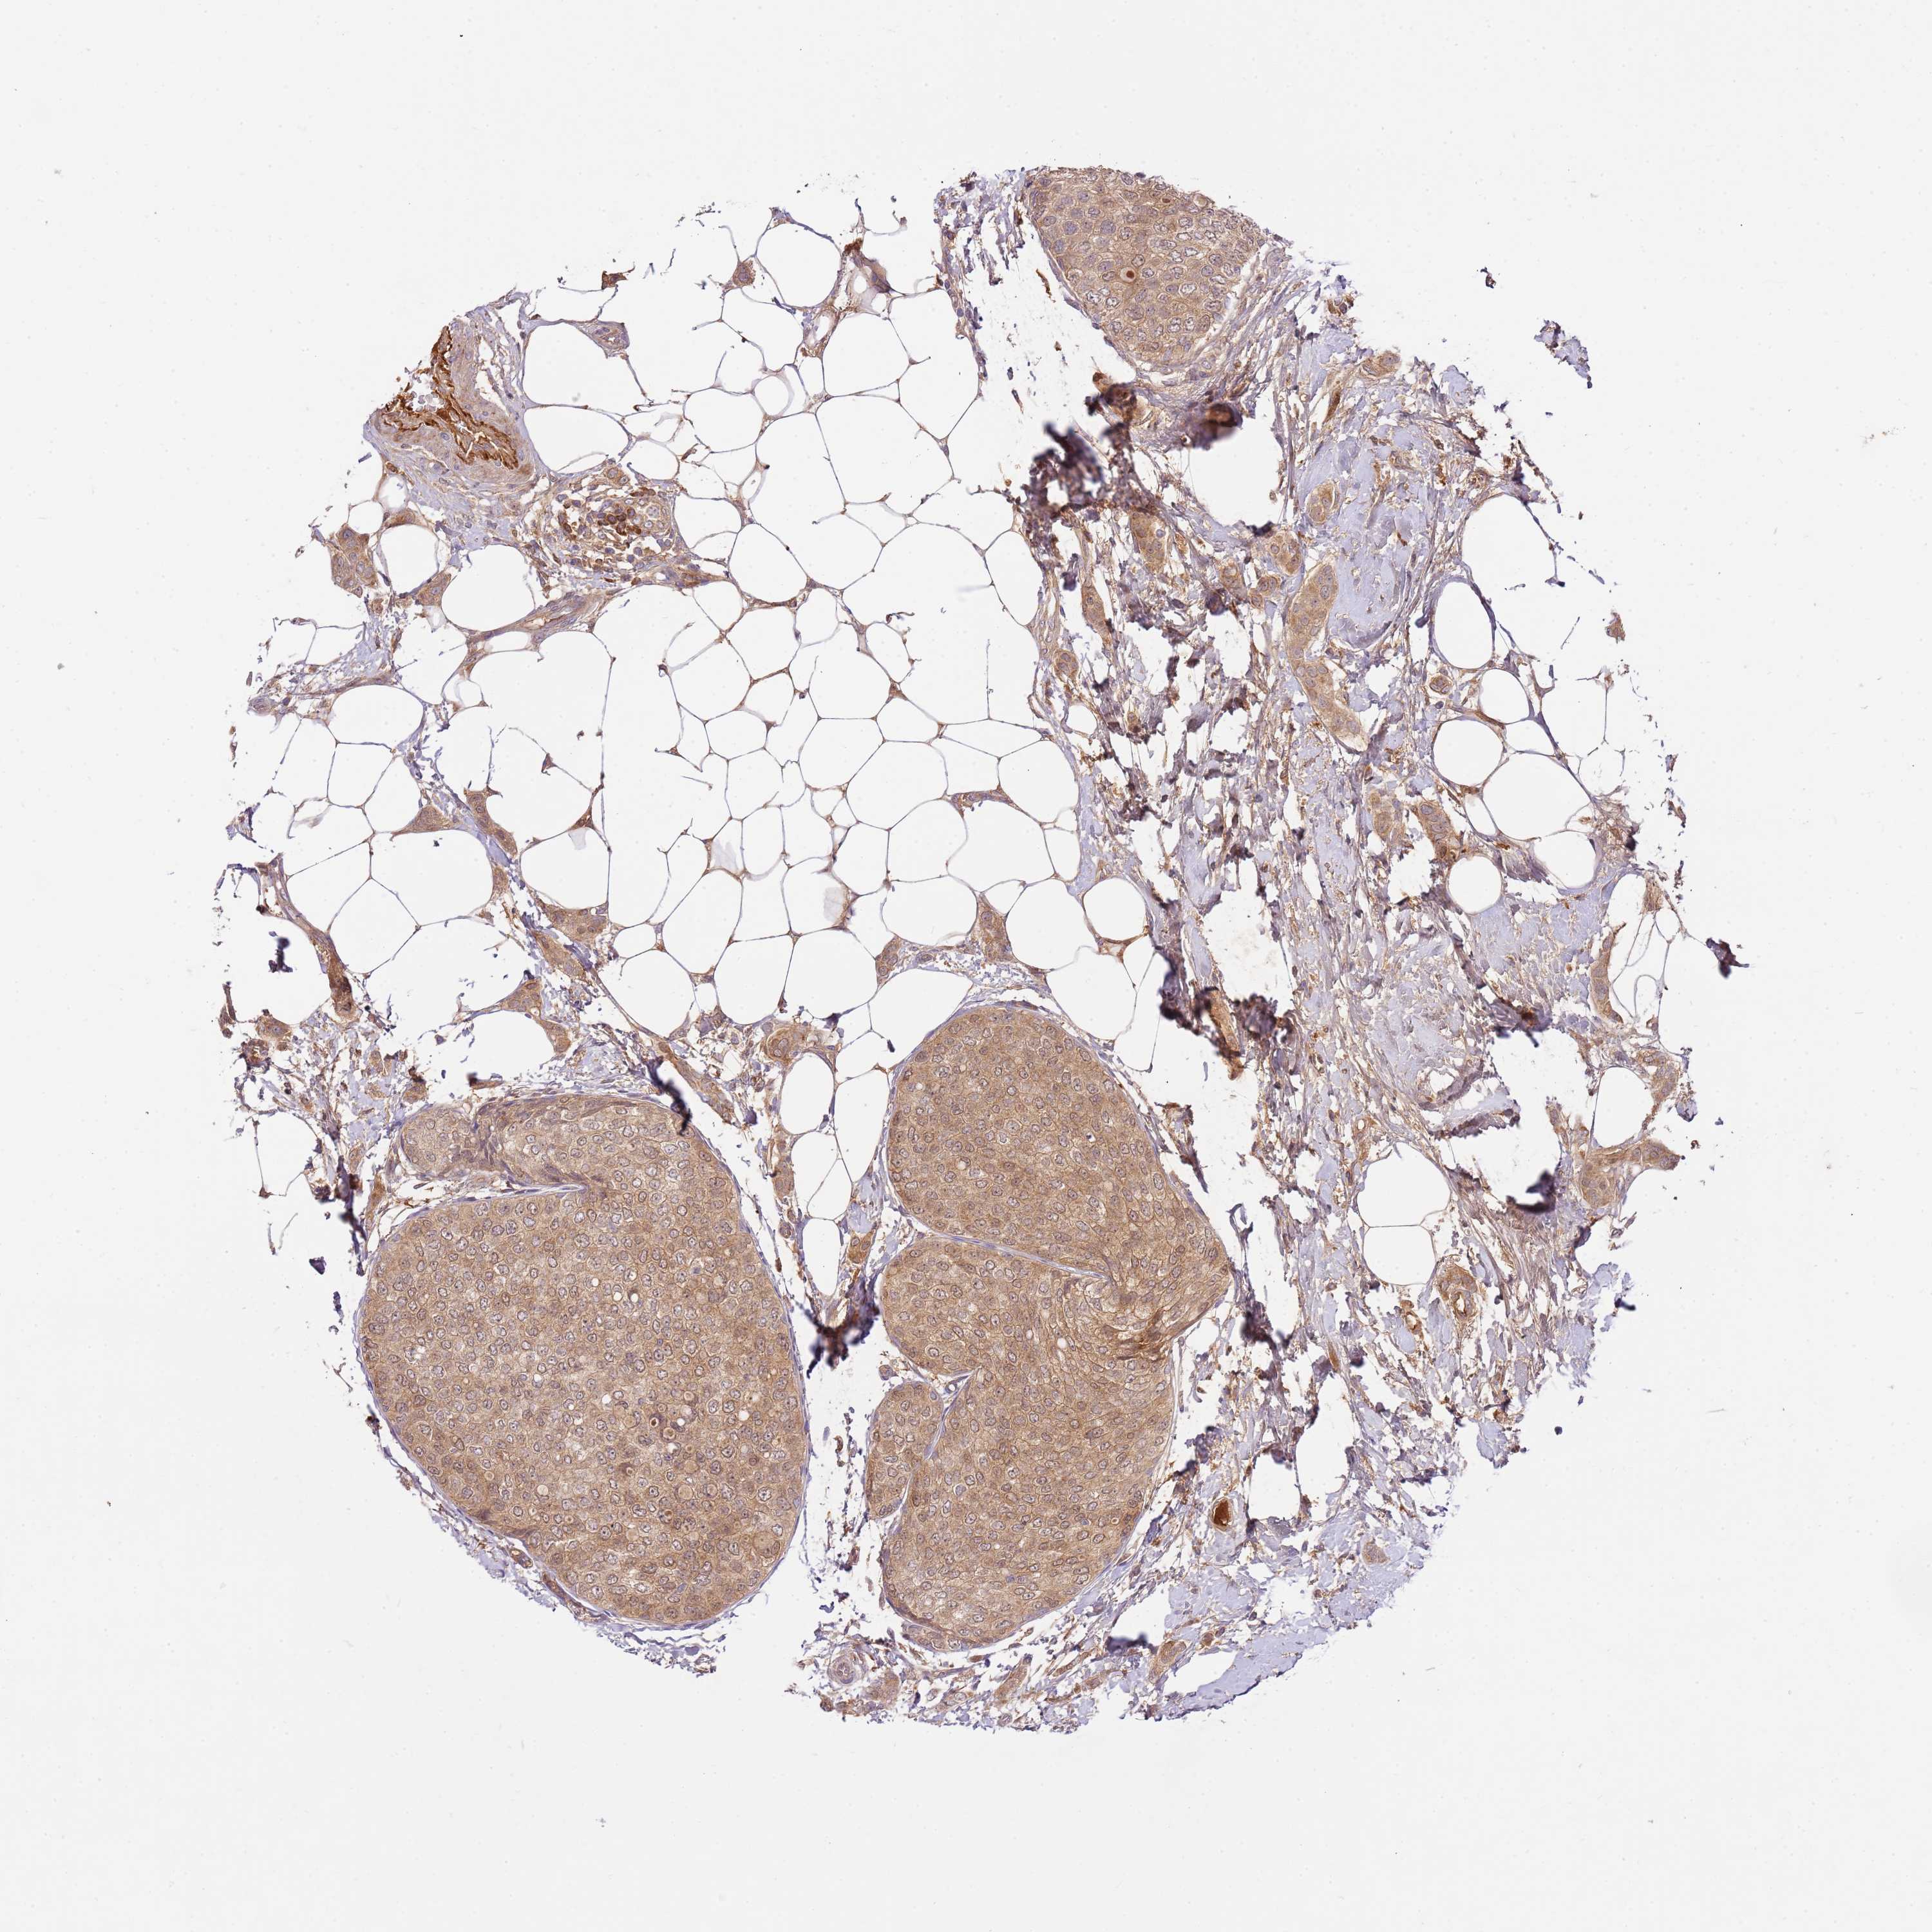

BRCA TCGA BRCA VALIDATION PROTEIN EXPRESSION

Breast cancer

Human cancer